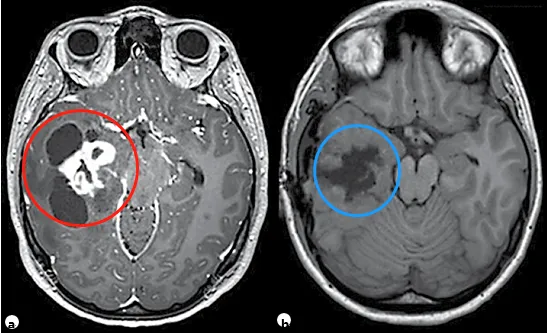

神经节神经胶质瘤(WHO I级)是最常见的致癫痫性肿瘤,尽管它仅占所有脑肿瘤的1%至4%。它往往发生于具有长期药物难治性癫痫病史的儿童和年轻人中。复杂部分性发作最为常见。尽管神经节神经胶质瘤倾向于出现在颞叶,但它可发生在神经轴的任何部位,包括颈髓连接处、松果体区和鞍上区域。颞叶外的位置与组织学异型性和间变性相关(间变性神经节神经胶质瘤;手术是这些肿瘤的主要治疗手段[见图3])。虽然有报道称存在恶性转化可能,但其通常是良性的。幕上神经节神经胶质瘤通常可以实现手术全切,因此是可治愈的,并为约80%的患者带来了Engel I级(无癫痫发作)的结局。为了进一步改善癫痫发作的控制,建议进行脑病灶切除联合邻近颞叶新皮质切除术。实现肿瘤全切的主要障碍是肿瘤的中线位置(如脑干),其他限制因素包括肿瘤边界不清、靠近重要功能皮层以及浸润了关键结构。

图3。一名11岁患儿,右颞部肿瘤表现为多发囊肿并伴有明显强化的实性瘤体部分。术前与术后轴位T1加权磁共振成像对比,提示肿瘤被完全切除,最终病理诊断为神经节神经胶质瘤。